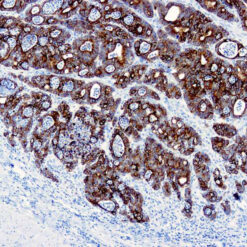

Cytokeratin (CAM5.2)

Anti-Cytokeratin (CAM 5.2) reagent has a primary reactivity with human keratin proteins that correspond to Moll’s peptides #7 and #8, Mr 48 and 52 kilodaltons (kd), respectively. Cytokeratin 7 and 8 are present on secretory epithelia of normal human tissue but not onstratified squamous epithelium. Anti-Cytokeratin (CAM 5.2) stains most epithelial-derived tissue, including liver, renal tubular epithelium, and hepatocellular and renal cell carcinomas. Anti-Cytokeratin (CAM 5.2) might not react with some squamous cell carcinomas.

| Positive Control Tissue | Colon, Lung, prostate and breast tissue. |